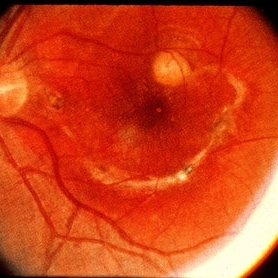

40-year-old man from South America was referred for a peripheral retinal scar in his left eye. He had a history of conjunctivitis as a child with exposure to multiple pets (cats and dogs). Fundus photo revealed a peripheral scarred sub-retinal granuloma located superior nasal with a retinal fold and traction extending to the optic nerve.

Photographer: The New York Eye & Ear Infirmary Department of Medical Imaging

Condition/keywords: toxocariasis